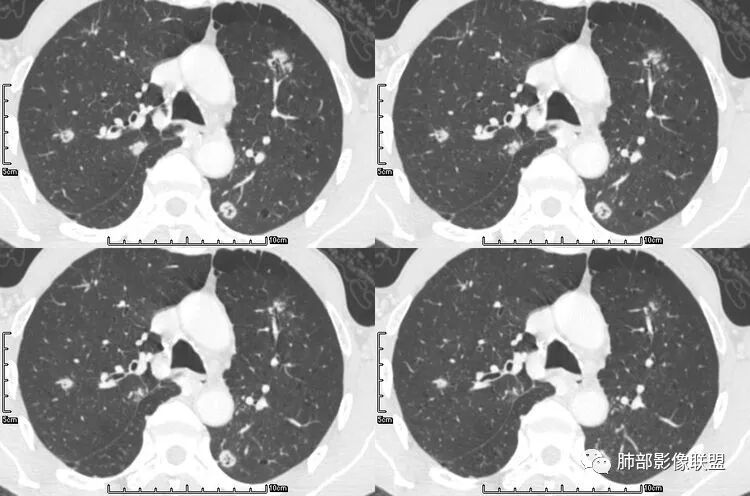

肺腺癌伴双肺转移,双肺多发环形薄壁囊腔转移瘤;

颈部淋巴结病检:腺癌;双肺多发薄壁囊腔性转移瘤;

病史为结肠腺癌;双肺多发薄壁囊腔转移瘤

其中囊样空洞和小环形空洞属于薄壁空洞,泡样空洞和不规则空洞属于厚壁空洞,其中腺癌空洞型肺转移瘤主要表现为小环形空洞,以下3个病例均表现为小环形空洞的转移瘤: